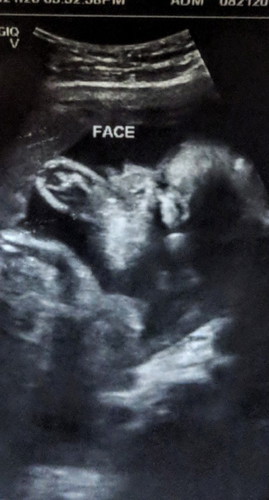

My first ultrasound indicates EDD on Nov 24, (3months ago) last week I had my second ultrasound, gender was known and EDD was Nov 11. Which is more accurate? First time mom here. π

Your very first ultrasound mommy. Sa Ultrasound po kasi nag-iiba talaga ang edd based sa laki ni baby but don't worry mommy kasi magkalapit lang naman ang due date mo. Always remember na sa edd po 2weeks before and after po possible lalabas si baby.

According po sa OB ko before. First transvaginal ang pinaka accurate of all ultrasounds. +/- 2 weeks naman po sa EDD usually ang paglabas ni baby. π